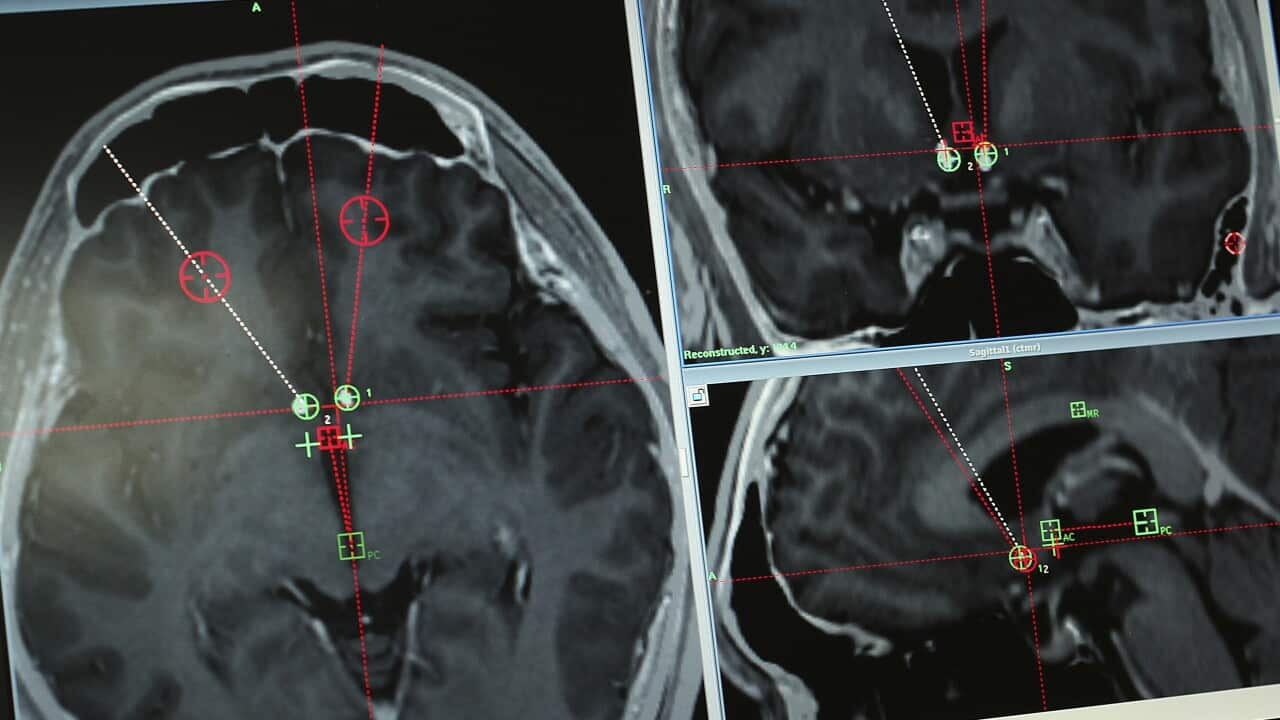

大家可能奇怪為何這般昂貴?原來除了以吊針輸送藥物的費用外,還要支付治療初期密集式使用 MRI (磁力共振掃描) 的開支。